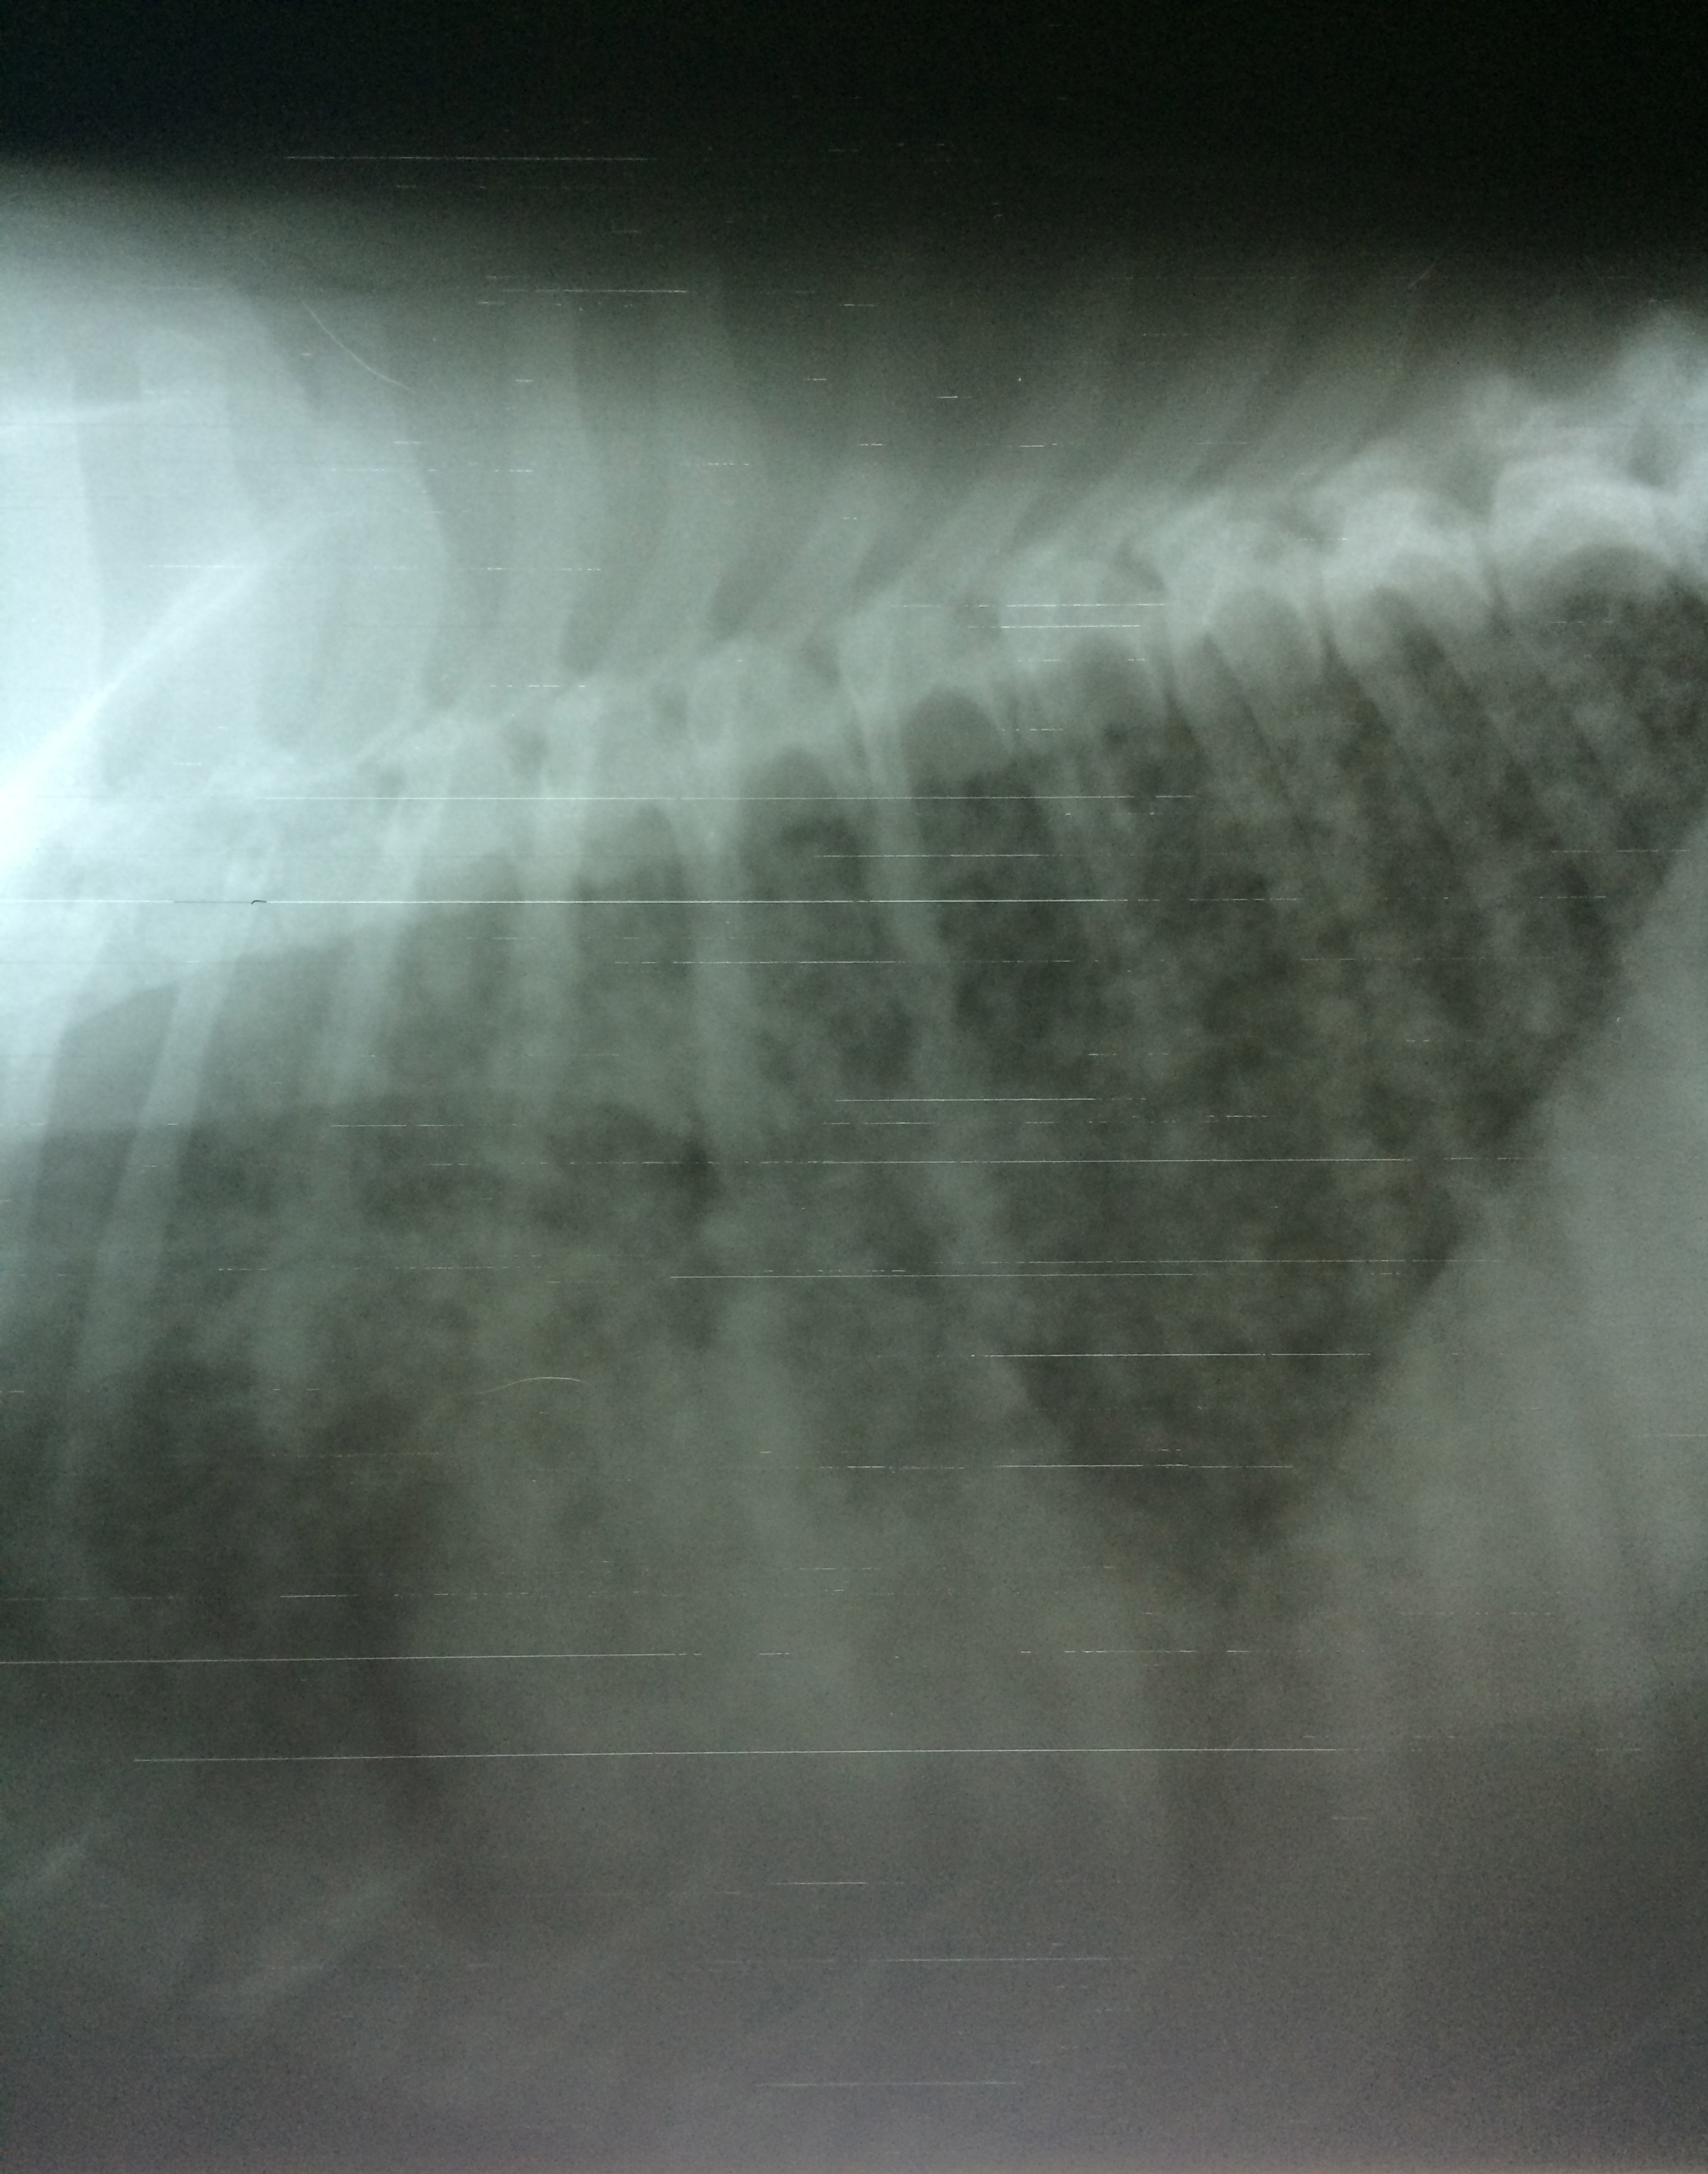

Blastomycosis Dog Chest X Ray . It is a pyogranulomatous fungal infection and the respiratory system is the. The infective form of the organism, the mycelial phase, is most likely to be found in sandy,. Objective —to identify radiographic patterns in dogs with pulmonary blastomycosis and radiographic factors associated with outcome. Blastomycosis is a systemic fungal infection caused by the dimorphic fungus blastomyces dermatitidis. Symptoms are dog coughing, breathing problems, fever, draining skin lesions, and fever. Blastomycosis in dogs is a potentially deadly canine disease caused by a fungus found in damp soil where mold is present. Animals —125 dogs with pulmonary blastomycosis. Pulmonary blastomycosis refers to respiratory infection with the organism blastomyces dermatitidis.

Animals —125 dogs with pulmonary blastomycosis. Objective —to identify radiographic patterns in dogs with pulmonary blastomycosis and radiographic factors associated with outcome. The infective form of the organism, the mycelial phase, is most likely to be found in sandy,. Blastomycosis in dogs is a potentially deadly canine disease caused by a fungus found in damp soil where mold is present. Pulmonary blastomycosis refers to respiratory infection with the organism blastomyces dermatitidis. Symptoms are dog coughing, breathing problems, fever, draining skin lesions, and fever. Blastomycosis is a systemic fungal infection caused by the dimorphic fungus blastomyces dermatitidis. It is a pyogranulomatous fungal infection and the respiratory system is the.